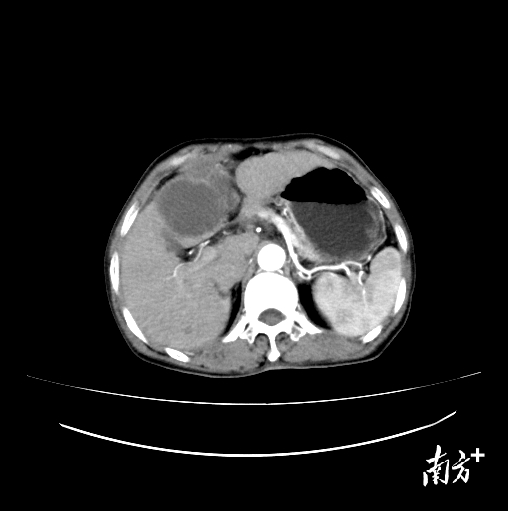

在陈逢生和家属的反复鼓励下,王阿姨尝试接受治疗免疫联合靶向治疗和辅助中医药治疗。半年后,肝癌肿块明显缩小,肿块边缘清楚,强化消退,这意味着,肿块的活性得到了明显抑制!

治疗后肝癌肿块明显缩小,活性得到明显抑制。